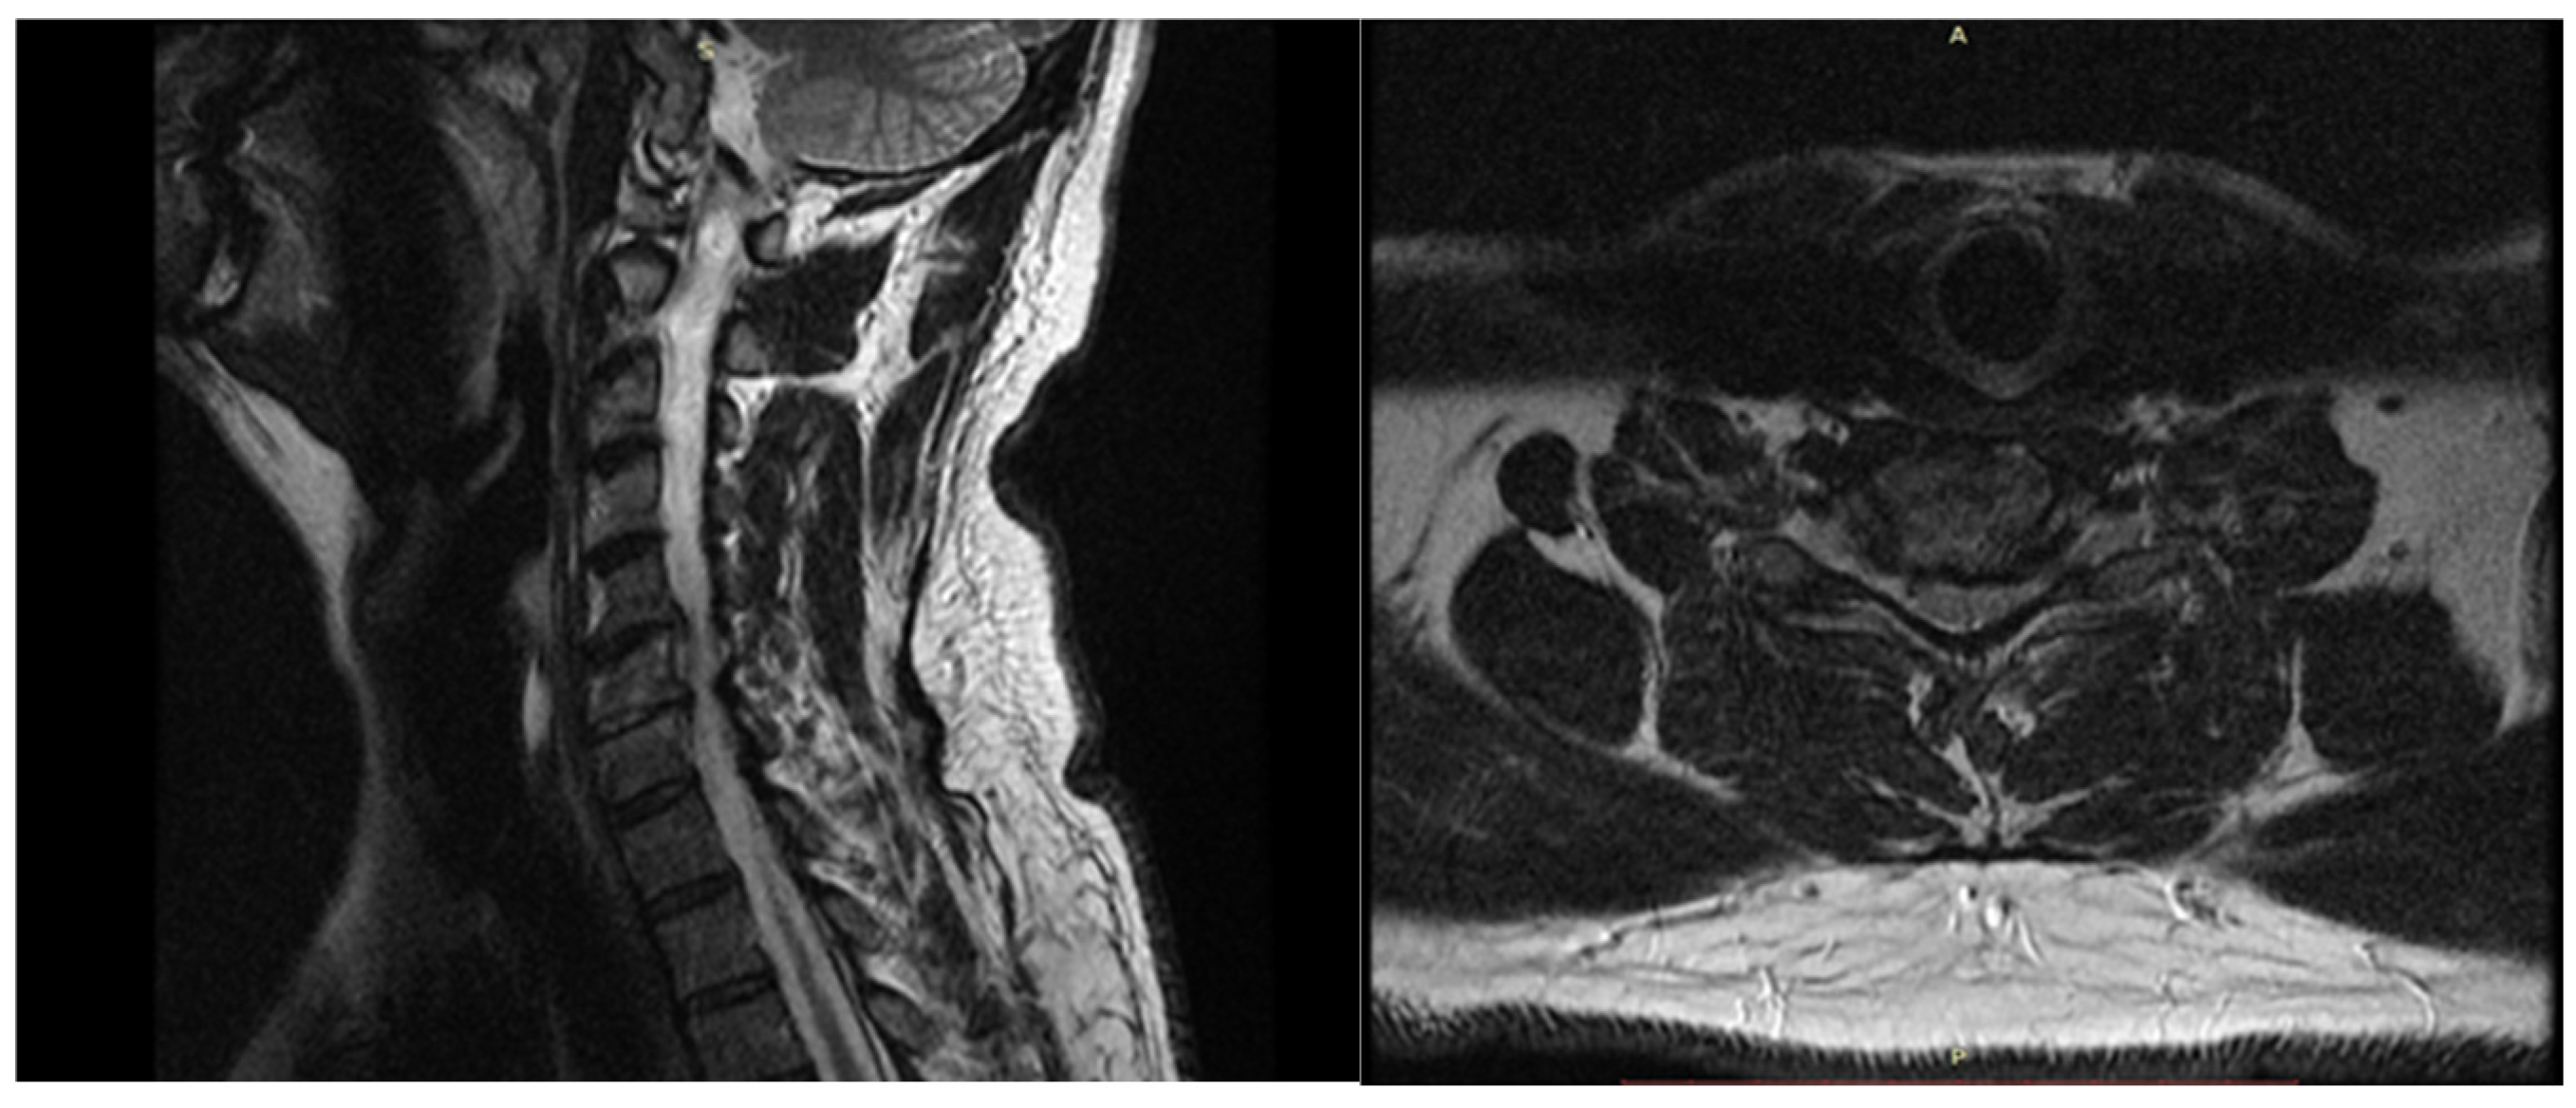

The preoperative evaluation included a detailed anamnesis and a review of complete medical records to ensure adherence to the study’s inclusion/exclusion criteria. All patients underwent an MRI (Scheme 1), but none had preoperative neurophysiological tests, such as EMG, SSEP, or MEP, as these are not part of the standard procedure. Preoperative assessments involved thorough neurological examination, manual muscle testing (MMT), the Numeric Pain Rating Scale (NPRS), and the Neck Disability Index (NDI) questionnaire. Postoperative assessments of pain and NDI were conducted one month after surgery. In all cases, we used multimodal IONM, which included somatosensory-evoked potentials (SSEPs), motor-evoked potentials (MEPs), and spontaneous electromyography (EMG).

Scheme 1. T2-weighted MRI images—sagittal and axial view of the cervical spine.